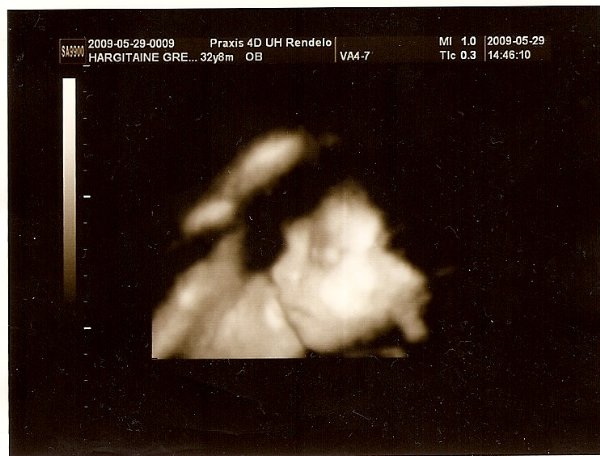

[quote="vicger"][ írta:vicgerimg]https://www.babanet.hu/tarsalgo/attachments/1243880636.351.jpg[/img]

Annyira jó ez a kép szerintem!!!